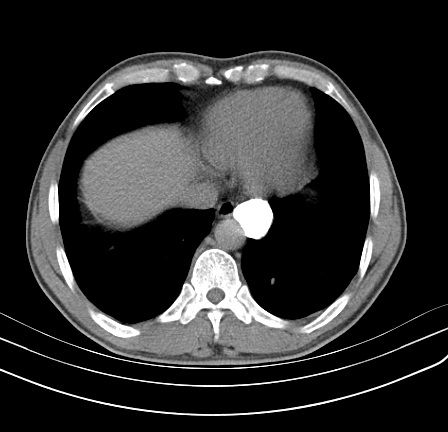

以下是引用影像孺子牛在2009-5-20 23:18:00的发言:[br]左侧后心膈角处类椭圆形钙化灶,最常见的是淋巴结钙化,但太大了不支持,其它如食管囊肿钙化、实性畸胆瘤等。何东西钙化真不好定。

以下是引用zbp537在2009-5-20 20:52:00的发言:[br]钙化灶,来源不好说。